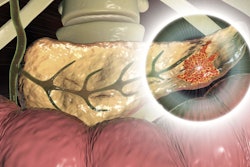

In their study, the researchers sought to develop an AI tool that can assist clinicians in identifying patients at high risk for pancreatic cancer, an aggressive cancer that is often undetected until later stages and has a relatively poor prognosis, according to co-first author Davide Placido, a doctoral candidate at the University of Copenhagen.

As there are currently no reliable biomarkers or screening tools that can detect pancreatic cancer early, the group sought to develop an AI tool that could help clinicians identify high-risk patients. These patients could then be enrolled in prevention or surveillance programs and hopefully benefit from early treatment, according to Yuan.

Although it's difficult to exactly pinpoint the diagnosis patterns that predicted risk, the researchers uncovered significant associations with certain clinical characteristics and the higher risk of pancreatic cancer development. These included diagnoses of diabetes, pancreatic and biliary tract diseases, and gastric ulcers.